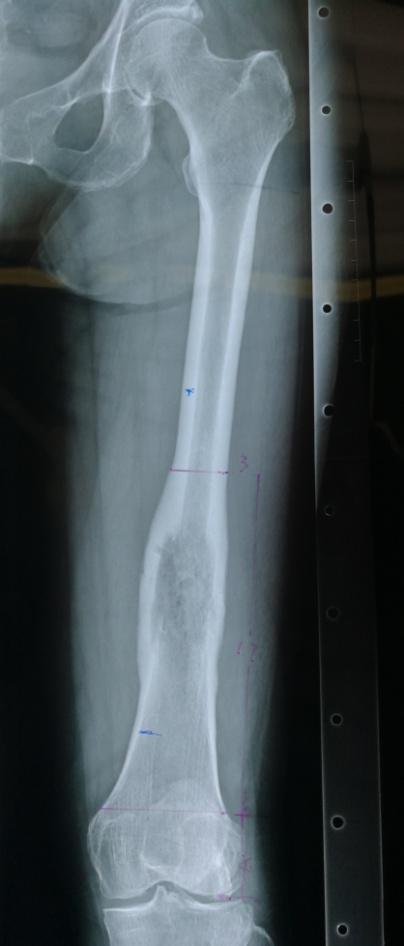

骨病骨肿瘤科近日成功实施“带血管腓骨复合大段异体骨移植手术”。患者冯女士,因左侧大腿疼痛3个月,经检查提示左股骨恶性肿瘤。患者慕名就诊我院骨病骨肿瘤科,科主任胡勇教授团队经反复讨论并细致规划,最后决定为其实施左股骨恶性肿瘤广泛切除,行生物重建手术(即带血管腓骨复合大段异体骨重建股骨),手术过程顺利,患者术后恢复良好康复出院。

大段异体骨复合带血管腓骨用于四肢长骨骨缺损重建的力学和生物学优势,在力学方面,早起大段异体骨的载荷与中晚期带血管腓骨愈合后的载荷互补,为重建后功能康复过程中的不同阶段的力学支撑提供保证。在生物学方面,大段异体骨提供了骨量和生物学支撑体;血管化腓骨作为活骨其愈合过程无须爬行替代;血管化腓骨为大段异体骨提供了内活化表面, 并可促进异体骨和宿主骨断端愈合。